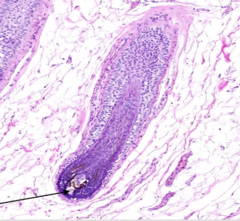

hair bulb

Front

what is the name of this portion of the hair follicle?

Back